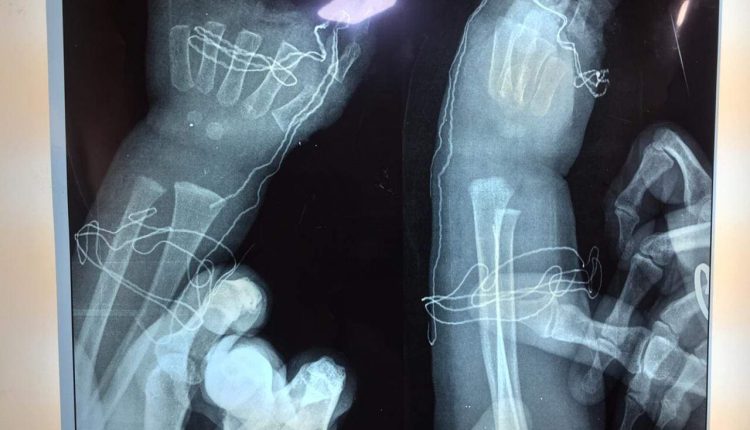

تمَكن فريق طبي وصحي مُتخصص في مدينة الإمام الحسين ( ع ) الطبية بكربلاء المُقدسة ، من إعادة وترميم ” أصابع الكف الأيسر المبتورة ” لطفل من أهالي المحافظة بعمر ( 3 ) سنوات بعد أن تعَلقت بماكينة فرم اللحوم ” ، في حين بيَن الفريق المُعالج إن ” الطفل غادر المدينة الطبية وهو بحالة مُستقرة عقب رقوده في ردهة الكسور مدة أربعة أيام ” . وأفاد رئيس الفريق ، أخصائي جراحة العظام والكسور، الدكتور هيثم محمود الأسدي في حديث لـ ( وكالة درابين ) ، اليوم الثلاثاء ، إن ” طوارئ المدينة الطبية ، إستقبلت الطفل محمد رضا بهاء حكمت ، وهو يُعاني من آلام شديدة ونزف من الطرف العلوي للكف الأيسر نتيجة تعَلقه ( الكف ) بماكينة فرم اللحوم ، تَسبب بأضرار شديدة بأصابع اليد والكف والرسخ ، يصعب معها إخراجها من الماكينة واليد بداخلها ” . وأضاف الأسدي ، إن ” الملاكات العاملة في عمليات الطوارئ تعاملت بمهنية عالية مع الوضع الصحي للطفل ، وقُدمت له الإسعافات الأولية اللازمة ، ومن ثم تهيئته لإجراء عملية طارئة له ، سبقها إبلاغ ذويه وإستحصال موافقته عليه لصعوبة الحالة ومدى تضرر الكف الأيسر ” . وتابع ، قمنا بالإستعانة بجهاز قطع الحديد ( كوسرة كهربائية ) لإنقاذ اليد من البتر ” . وزاد الأسدي ، إن ” العملية التي إستغرقت ( ساعتين ) متواصلة ، وتكللت بالنجاح التام ، شهدت تقطيع الجزء المعدني من الفرامة العالقة في الطرف العلوي الأيسر لتقليل الأضرار على الجزء المُصاب من اليد والرسخ ” ، مُبيناً إنه ” بعد نجاح عملية التقطيع وتحرير الطرف العلوي ، وجدنا أصابع اليد اليسرى مُتضررة بشكل كبير ومُهشمة الى قطع صغيرة ، ليتم بعدها إنقاذ إصبعين من اليد ( الإبهام والخنصر ) مع هندمة الجرح وترميم الأصابع ، ومن ثم تحويله الى ردهة الكسور وسط متابعة وعناية دقيقة لوضعه الصحي ، ومغادرته منها وهو بحالة مُستقرة عقب رقوده فيها مدة أربعة أيام ” . ولفت الأسدي ، إن ” الفريق المُساعد له ، كان مؤلفاً من أخصائيي الجراحة التجميلية والتخدير ، الدكتور محمد مصطفى ويس ، والدكتور كفاح عودة ، ومقيم أقدم كسور ، الدكتور سنان صلاح العامري ، ومقيم أقدم جراحة تجميلية وتقويمية ، الدكتور أمير حسن السعدي ، والمُمرضين ، حيدر كريم عبد ، ومحمد حمزة موسى ، وحسين داوود محمد ، وعبير عبد العظيم ، ومساعدي التخدير ، أحمد وصفي ، وعامر علي كاظم ” .